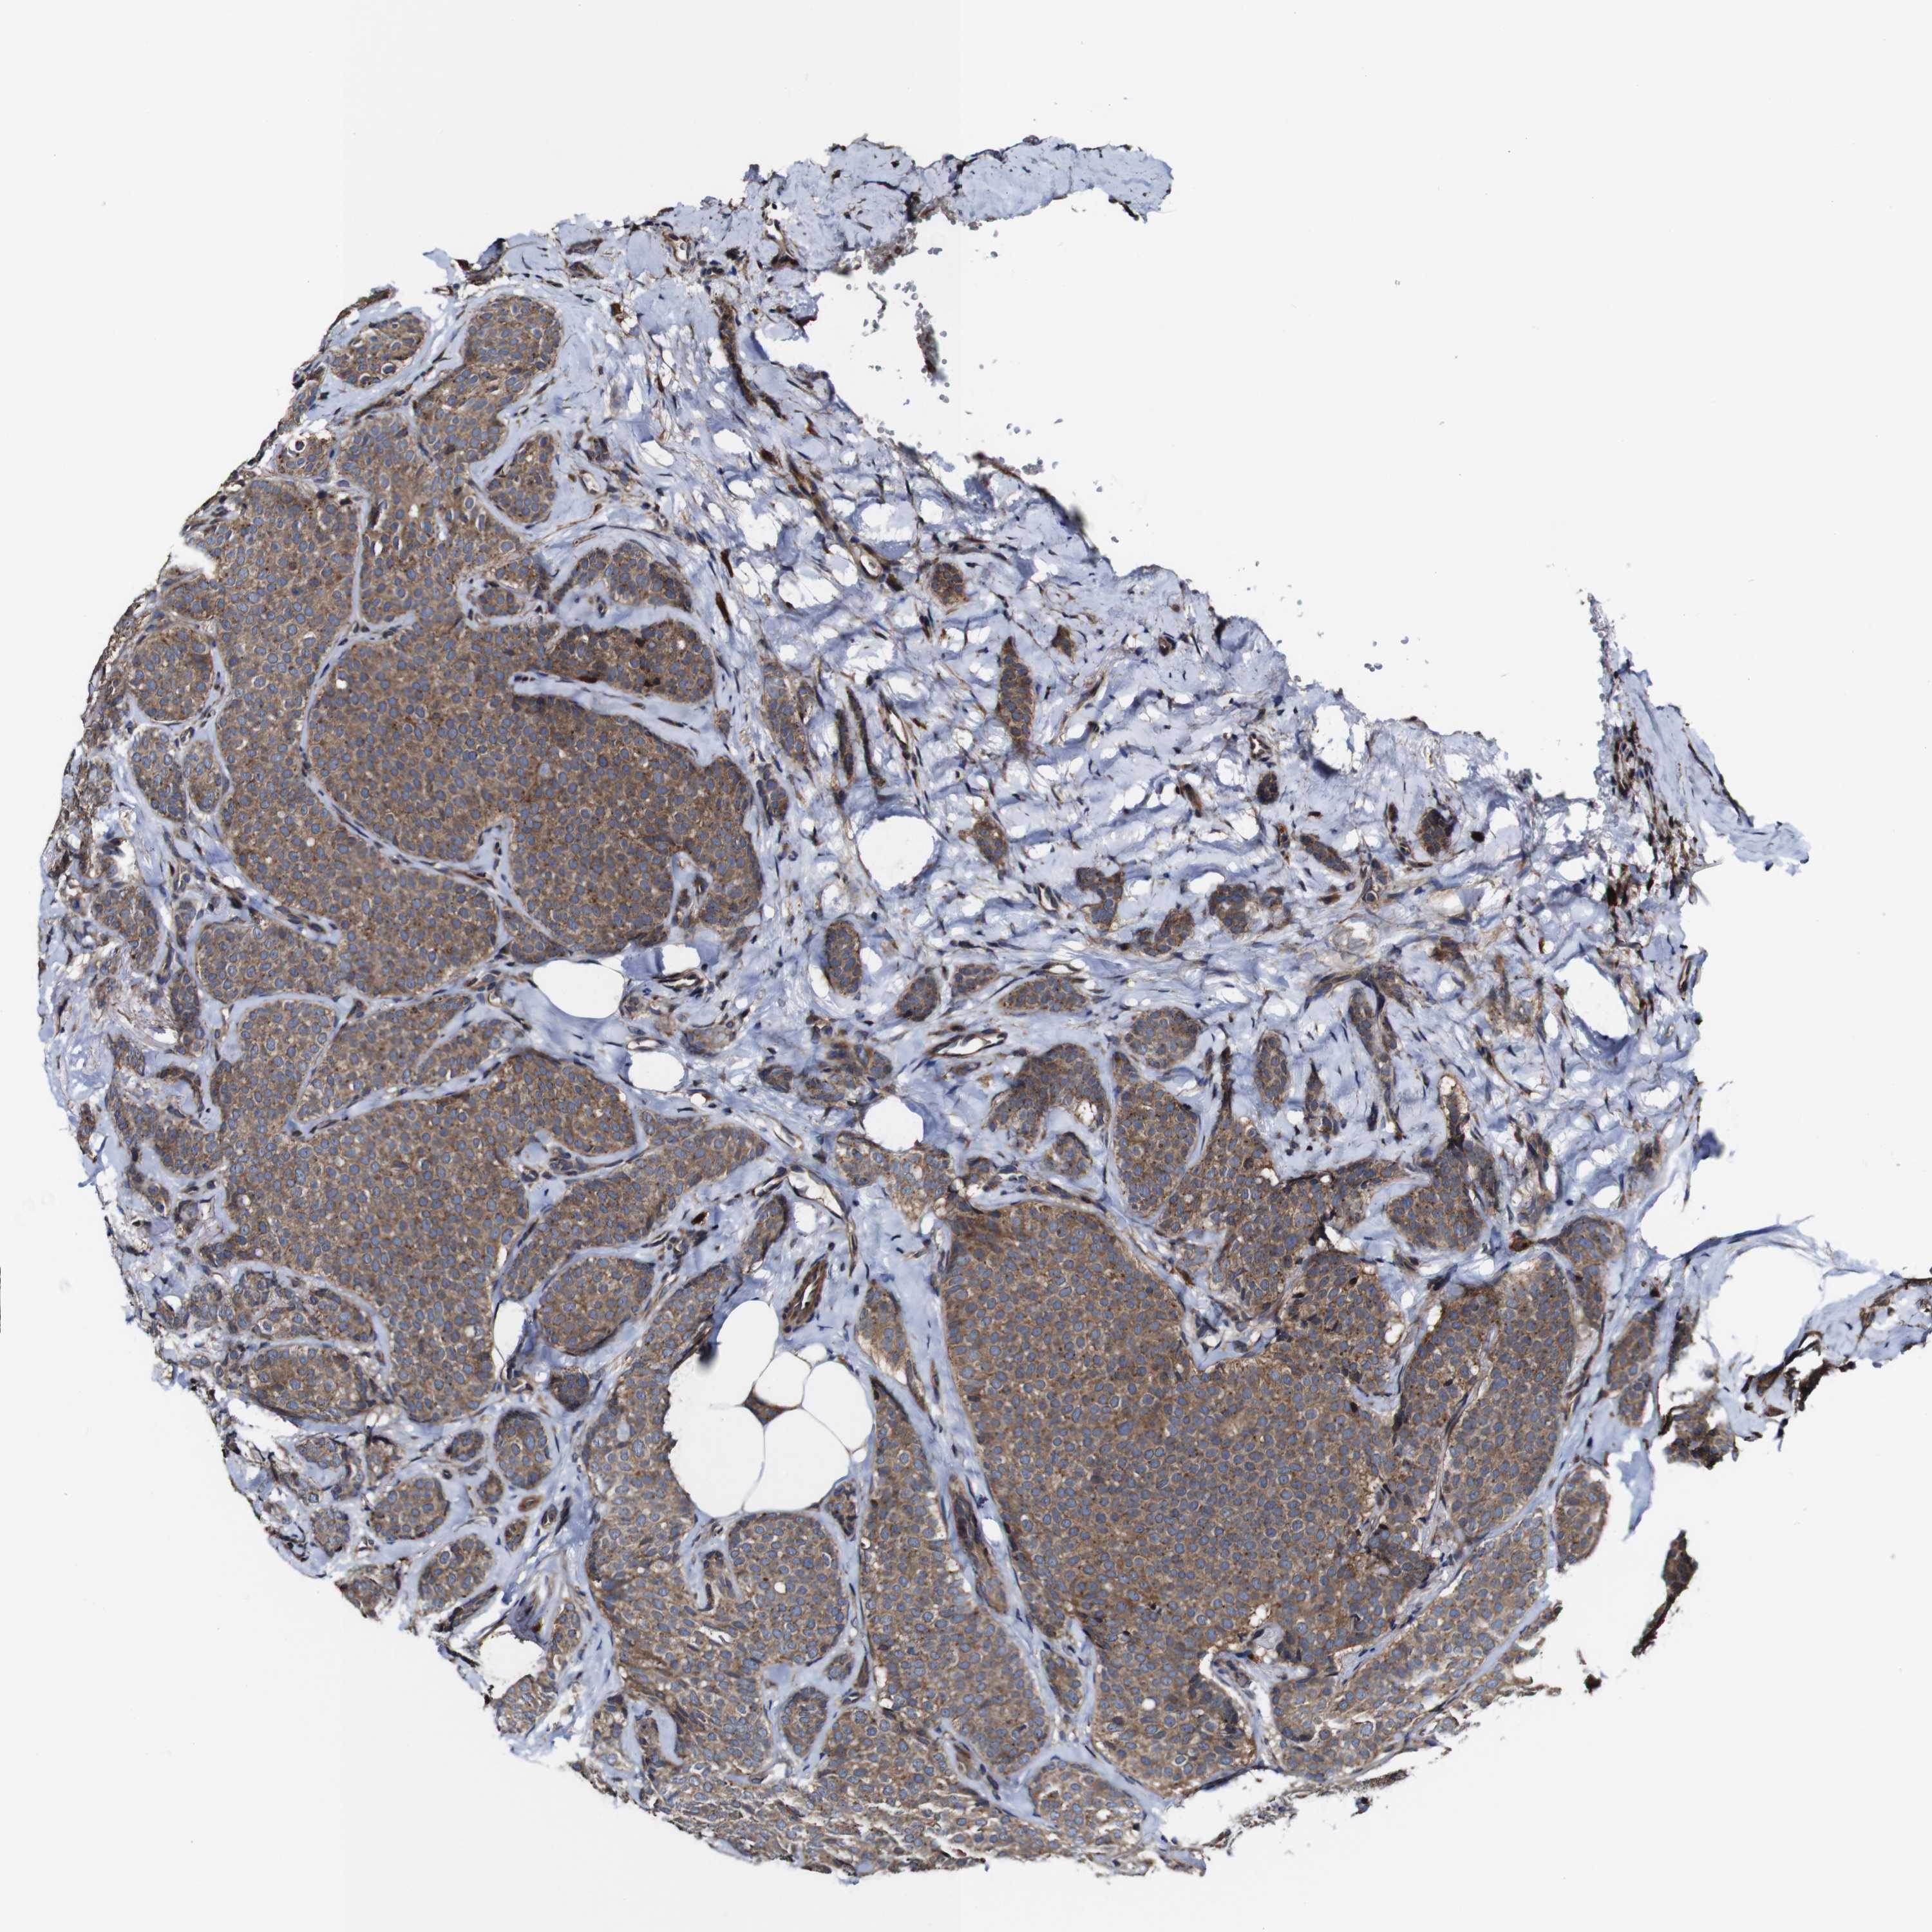

CANCER BREAST CANCER Show tissue menu

BRCA TCGA BRCA VALIDATION PROTEIN EXPRESSION